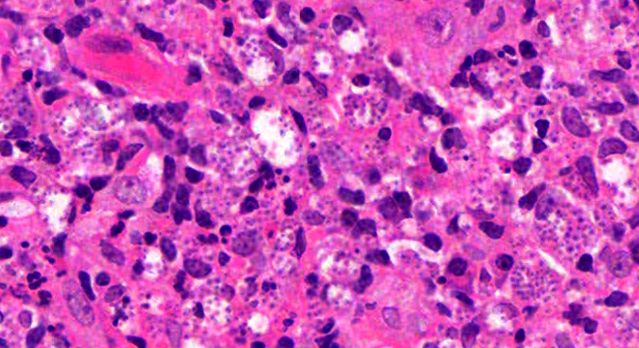

Dermatopathology Case 238 Get link Facebook X Pinterest Email Other Apps June 20, 2022 A 25 year old male with an ulcerated lesion on the shoulder. History of recent travel to a tropical country. Answer Get link Facebook X Pinterest Email Other Apps Comments